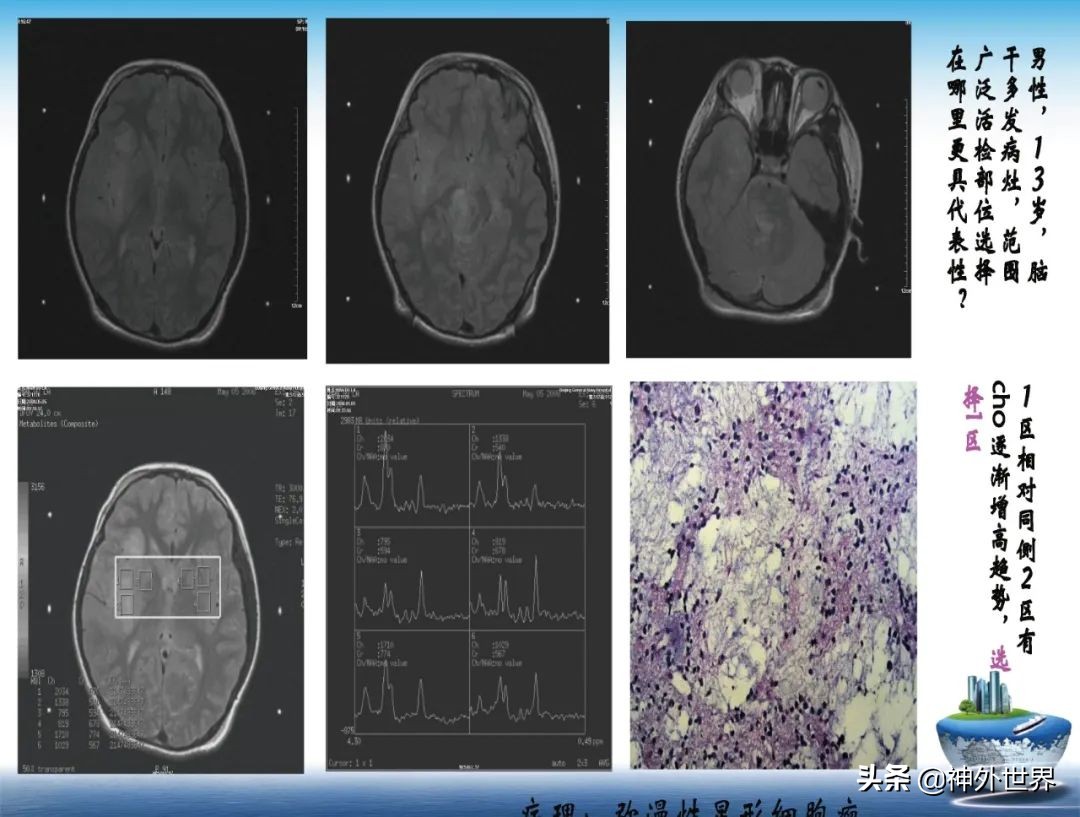

专业方向:颅内肿瘤的显微外科手术切除,颅咽管瘤综合治疗具有特色;在立体定向脑内病灶活检、立体定向清除脑干血肿、立体定向间质内放疗、机器人辅助神经外科手术方面具有专长。